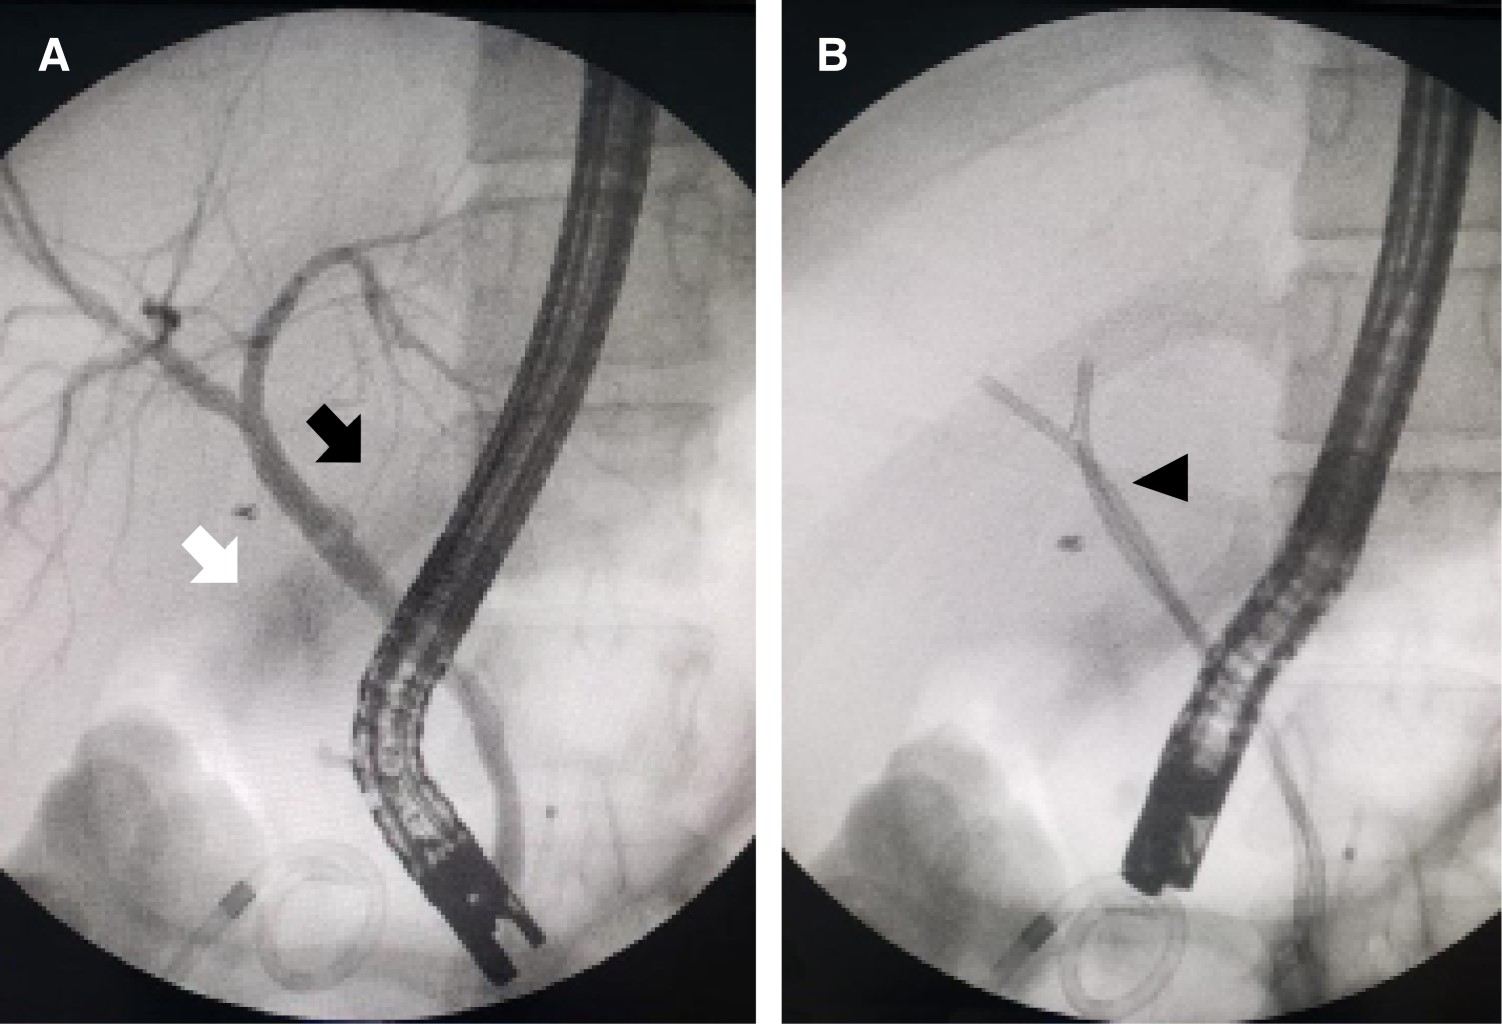

Introduction: laparoscopic cholecystectomy is the gold standard for gallstone disease, however, it is not free of complications, such as hemorrhage, seroma, biloma, biliary leakage, surgical wound infection and bile duct injury, being the presence of aberrant ducts one of the main risk factors. The anatomical variations of the biliary tract are due to alterations in the embryological development, it is important that the surgeon knows how to recognize them, since during cholecystectomy there is a risk of ligation, section, biliary leak or stenosis of an accessory or aberrant duct. Biliary leaks have increased since the standardization of laparoscopic cholecystectomy, with a frequency of approximately 0.3-0.5%. Endoscopic retrograde cholangiopancreatography (ERCP) is the ideal study, since it confirms the diagnosis by identifying the site of biliary leakage and during the same procedure sphincterotomy and stent placement can be performed, allowing closure of the defect, with a success rate of more than 90%. Clinical cases: we present two cases of biliary leakage after laparoscopic cholecystectomy secondary to the presence of anatomical variations of the extrahepatic biliary tract, both manifested by abdominal pain requiring hospitalization. In the first case the biliary leak was evidenced during ERCP and was resolved with the placement of a stent. The other case, having a negative ERCP and persistence of abdominal pain, underwent diagnostic laparoscopy, finding a biliary leak from an accessory duct, for which a new transoperative ERCP was performed for stent placement. Conclusion: these two cases are very interesting because despite being the same type of biliary leak, they presented differently, one at 72 hours postoperatively and the other at eight days. Likewise, one of them was resolved by ERCP and the other had a negative ERCP before the definitive diagnosis could be made. Therefore, a high index of suspicion of biliary leakage through an accessory or aberrant duct should be taken into account when faced with abdominal pain after laparoscopic cholecystectomy.

Figure 1